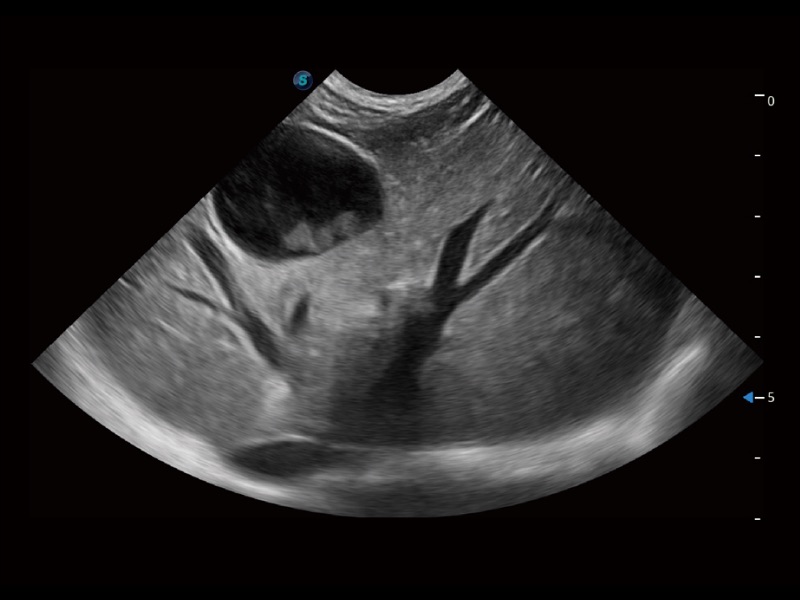

通過(guò)360度任意調(diào)節(jié)3條M型取樣線,在同一心動(dòng)周期上觀察心臟不同位置的運(yùn)動(dòng)曲線,得到準(zhǔn)確的心功能測(cè)量數(shù)據(jù),有效評(píng)估心肌運(yùn)動(dòng)及左心室功能。